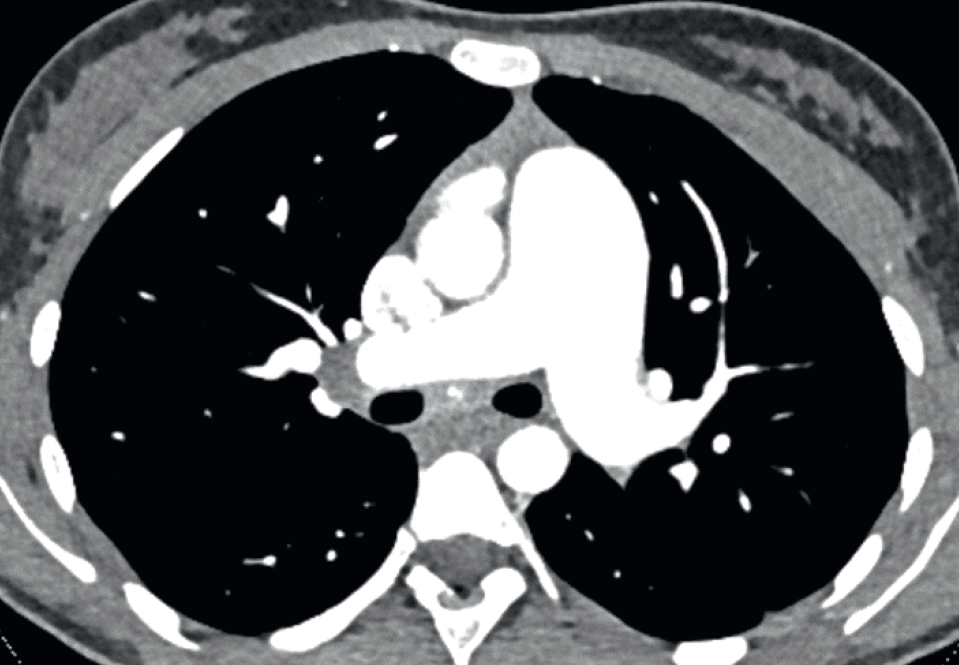

10h Innovations en imagerie vasculaire pulmonaire